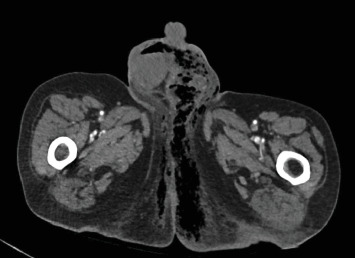

Peptic ulcer disease (PUD) results from erosion and ulceration of the upper digestive tract mucosa. Clinical presentations can vary from asymptomatic to severe complications such as perforation, strictures, or bleeding. Perforation can release enteric contents and gas into the abdomen, leading to intra-abdominal sepsis, requiring surgical intervention for source control and repair. We present a case of a 69-year-old male who developed both Fournier's gangrene and a right-sided pneumothorax secondary to a nontraumatic perforated duodenal ulcer. The patient underwent an emergent thoracostomy, laparotomy with Graham omentoplasty, and extensive debridement with successful outcome. While rare complications like pneumothorax and necrotizing soft tissue infections have been documented, their simultaneous occurrence from a nontraumatic ulcer perforation is unprecedented in literature. Previous reports suggest enteric contents can traverse retroperitoneal fascial planes and peritoneal defects to reach distant anatomical sites as a possible mechanism for these complications. This case highlights the potential for atypical presentations of PUD and the importance of comprehensive evaluation, early recognition, and prompt surgical intervention.